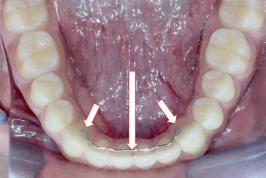

Contenção: nada ver com menstruação e infertilidade